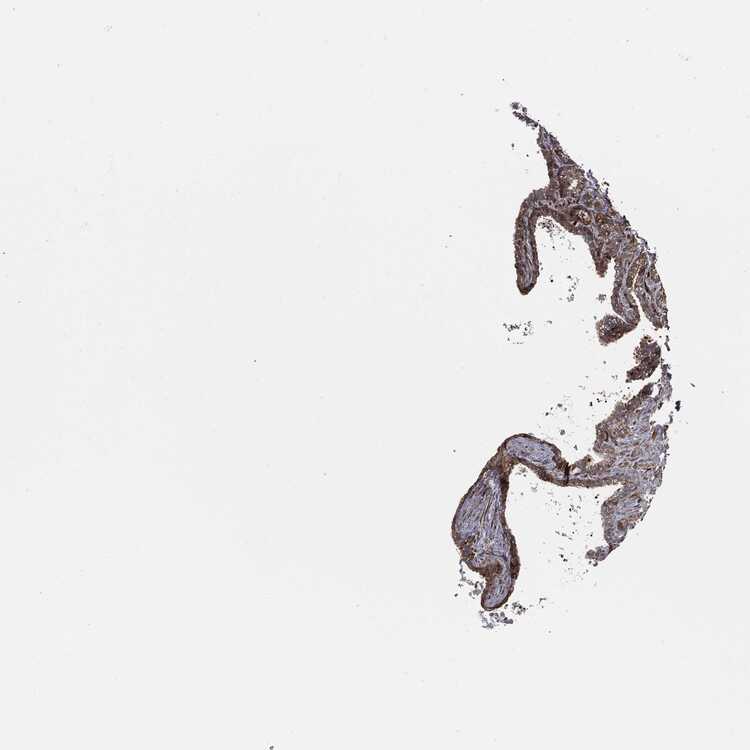

SEMINAL VESICLE - Antibody stainingi

Antibody staining in the annotated cell types in the current human tissue is reported as not detected, low, medium, or high, based on conventional immunohistochemistry profiling in selected tissues. This score is based on the combination of the staining intensity and fraction of stained cells.

Each image is clickable and will lead to virtual microscopy that enables deeper exploration of all samples and also displays staining intensity scores, fraction scores and subcellular localization as well as patient and tissue information for each sample.

Antibody HPA030419Antibody HPA030420Antibody HPA030422Antibody CAB025196Antibody CAB080286Antibody CAB080287

Glandular cells Not detectedNot detectedMediumMediumMediumMedium